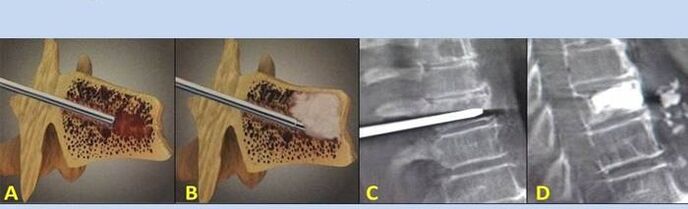

- Nucléoplastie – Ablation du noyau discal. L'opération soulage la pression sur les terminaisons nerveuses.

- Vertébroplastie par ponction – Méthode de stabilisation des vertèbres. Au cours de l’intervention, le médecin remplit les cavités de la colonne vertébrale avec du ciment osseux.